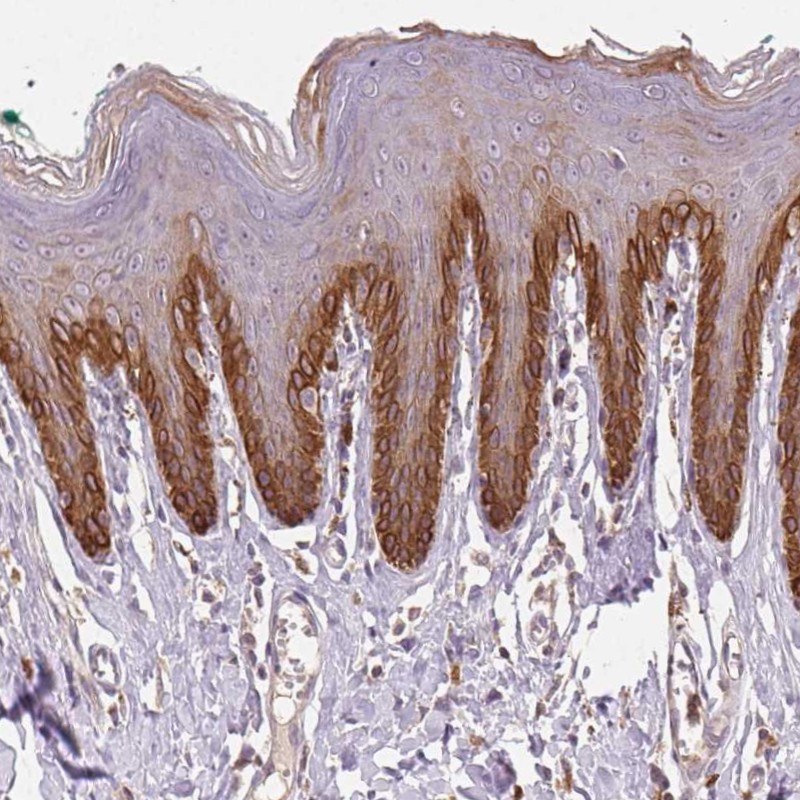

Immunohistochemical staining of human skin shows strong cytoplasmic positivity in basal layers of epidermal cells.